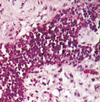

hydatidiform mole

74

hydatidiform mole

75

complete hydatidiform mole

76

hydatidiform mole

toe like extensions

extravillous thropho striking nuclear atypia

cyto-syncytiothropho

77

snow flakes

hydatidiform mole

78

invasive mole